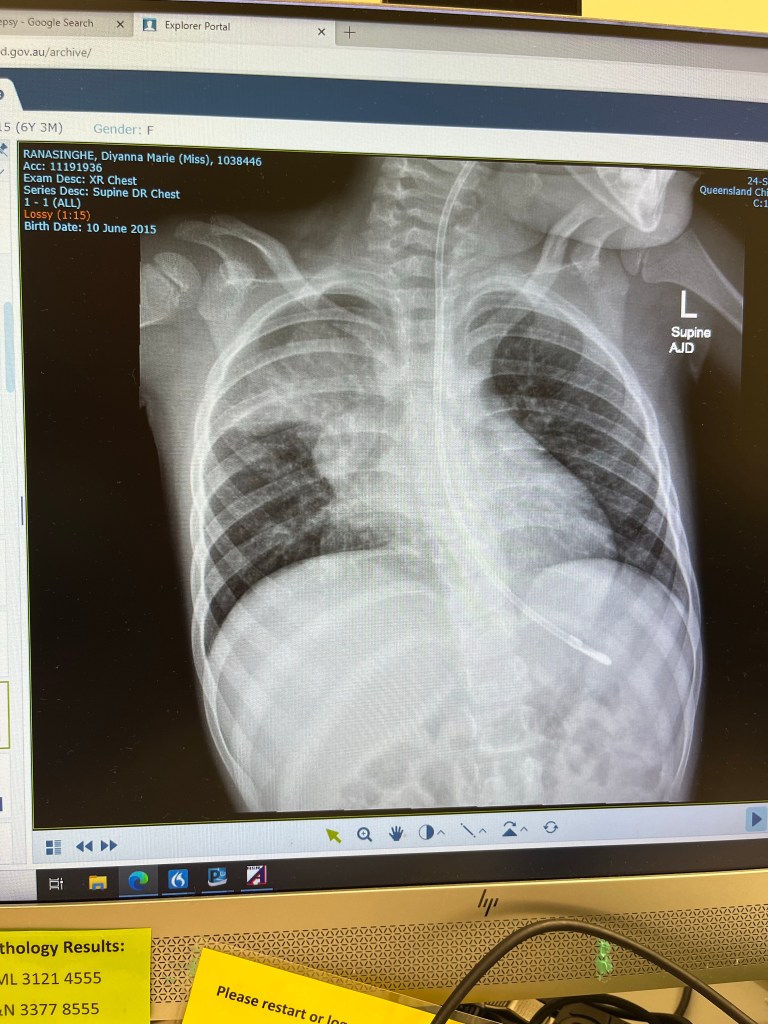

They say when it rains, it pours, and it all came to a head last year when our worst nightmare was realised. In May 2021 Diyanna caught a viral infection- her first in almost 2 years. The infection snowballed into a chronic infection that consumed most of her right lung. At the hospital she was found to be anaemic, the antibiotics were not working, her seizure activity was increasing… She was so weak.

Diyanna slowly pulled through and by the end of September, after nearly 3 months at the hospital, we were able to bring her home. Her right lung had sustained significant trauma to the point where feeding her orally was dangerous-She is now tube fed.

At almost the same time Dr David Kilner who had taken over as Diyanna’s respiratory specialist contacted us with a possible treatment for the damaged lung. Diyanna would be put on steroid treatment for almost 4 months with the hope that it would help reduce the inflammation there by stop further damage. It was a risky procedure as the side effects of the treatment could further deteriorate Diyanna’s health. Before leaving the hospital in September the head of the respiratory department had met us and said that he would not recommend such an intervention for a child like Diyanna and that we should accept and enjoy the time we had left. But Dr Kilner felt it would be the right choice for her and we trusted him. He was the only one who actually listened to Diyanna’s history and was willing to think beyond the norm.

An x ray taken in the middle of the therapy showed some improvement in her right lung. Another would be taken in August. Towards the end of the steroid program Diyanna got covid 19. But she managed to pull through without needing a hospital visit.

In the lead up to meet Dr Kilner in August another x-ray was taken. And we received the new we had been waiting for. The inflammation in Diyanna’s lung had subsided to the point where there was no trace of it on the x ray. Until another bronchoscopy is carried out the extent of the internal damage is not known but we can be hopeful that the outlook is not as bad as what it was a year ago.